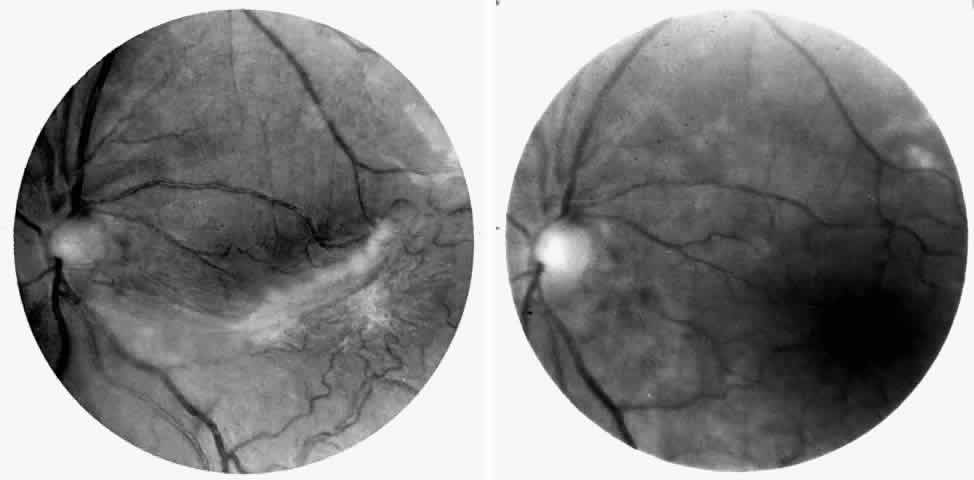

Vascular Tortuosity

Dilation and tortuosity of the retinal veins was one of the first recognized abnormalities of sickle cell eye disease. Although it is not pathognomonic of sickle cell disease, it reportedly occurs in up to 47% of patients with homozygous sickle cell anemia and 32% of patients with SC disease (Fig. 4).70 The significance of this venous tortuosity is unknown, and the incidence does not appear to be related to age.71

Fig. 4. A. Generalized vascular tortuosity, predominantly venous, in a patient with homozygous sickle cell anemia. B. Localized macular venous tortuosity in a patient with SC disease.

Angioid Streaks

Angioid streaks occur in association with sickle cell disease, with an overall incidence of less than 6%.72–75 The changes are more common in patients with homozygous sickle cell anemia and are age-dependent, occurring in 2% of sickle cell anemia patients less than 40 years of age versus 22% in those who are more than 40 years of age (Fig. 5).76

Fig. 5. A 45-year-old man with homozygous sickle cell anemia and angioid streaks (arrows).